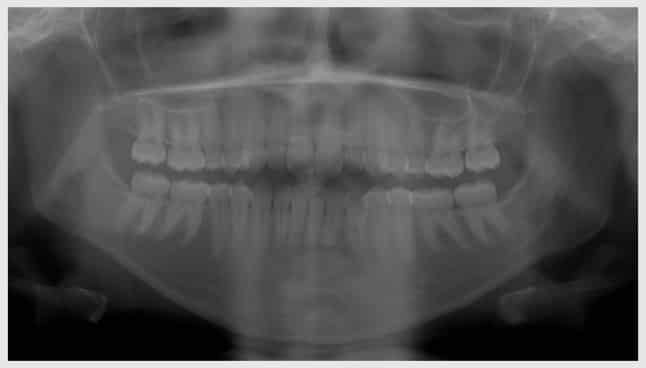

radiografia_panoramica

Equipe ImplArt

O Dr Roberto é um experiente especialista em Implantodontia. Somos uma Clínica Dentária de Implantes Dentários e Prótese Dentária, com foco no melhor de tecnologias avançadas como Implantodontia Digital. A ImplArt é considerada e melhor clínica de implante Dentário do Brasil pelo GCR.